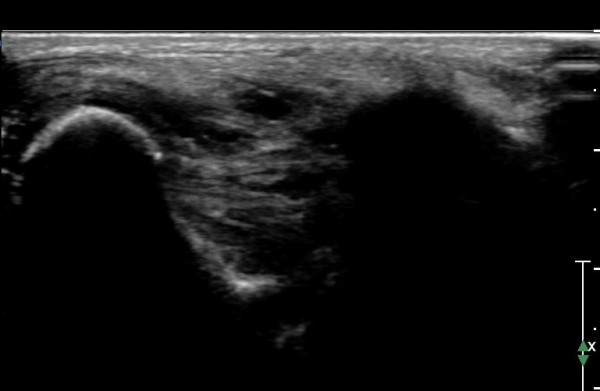

ÇϺΠ½ÅÀü ¶ì(inferior extensor retinaculum) ÀÇ frondiform Àδë Á¾´Ü¸é°Ë»ç¿¡¼­

frondiformÀδëÀÇ Àú¿¡ÄÚ ºÎÁ¾°ú °Å°ñÇÏ °üÀý °£°ÝÀÌ ¹ú¾îÁ® ÀÖ´Ù(»çÁø 8, 9).